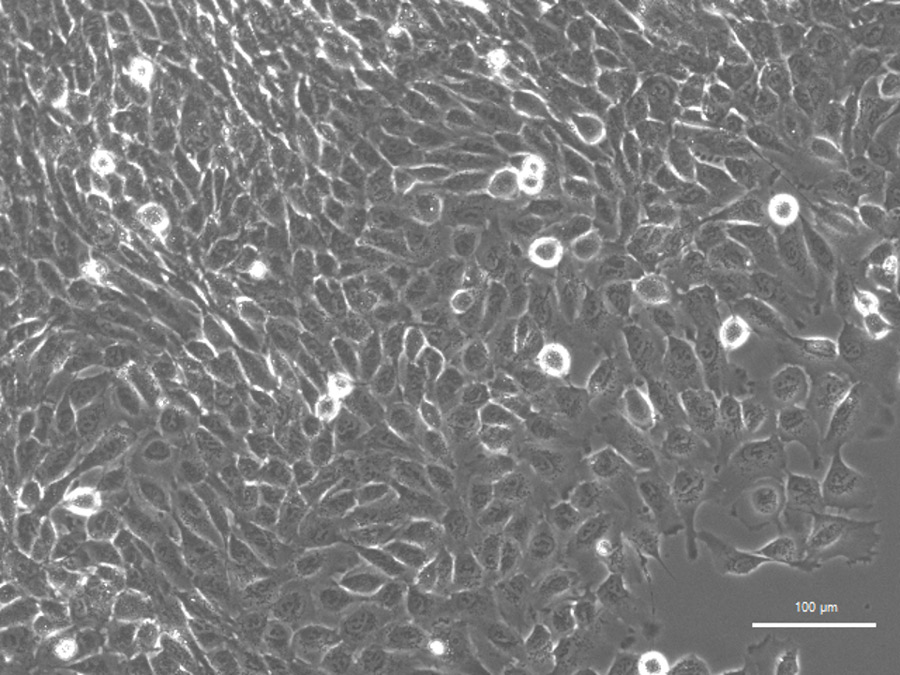

解决这个问题的一个方法是用人类细胞来模拟疾病。青木博士和他的同事们最近考虑了有希望用于这一目的的细胞来源,包括尿液来源的细胞(UDCs)。不同于其他可能的来源,如皮肤、肌肉或血液样本,细胞可以从尿液中无创获取,而且对病人没有伤害的风险。它们也可以从同一病人身上重复采集(而且成本低廉)。

尿液衍生的细胞已经显示出巨大模拟许多不同疾病的潜力。在最近的工作中,Aoki博士和他的团队开发了一个新的非侵入性系统,以在UDCS中模拟DMD。使用的细胞源于肾脏和泌尿道,具有干细胞的性质;也就是说,它们能够开发成几种不同类型的细胞,具有不同的功能。

该团队以两种方式使用udc。首先,他们成功地鼓励udc发育成健康的肌管(肌纤维细胞)。这是通过操纵一种名为MYOD1的基因实现的,该基因在肌肉发育中起着至关重要的作用。在这项工作中,该团队使用MYOD1有效地重新编程UDCs成为肌管。患有DMD的人会产生肌管在体外(在身体外)通过这种方法可用于探讨每个人疾病的精确性。